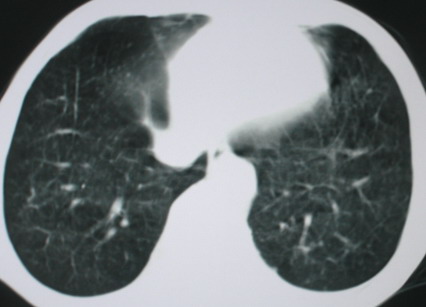

以下是引用医影拾贝在2008-6-3 18:48:00的发言:[br]双上肺弥漫性小结节影,纵隔窗内钙化淋巴结影,考虑血播性tb可能性较大,不除外肺ca可能

以下是引用卜一在2008-6-3 19:33:00的发言:[br]双肺结节,以双上肺分布为多,期间搀杂片状致密影及索条致密影。考虑:继发性肺结核伴血型播散可能性大。不除外肺泡ca的可能!另:椎体退变!

以下是引用panyishengct在2008-6-3 21:09:00的发言:[br]双上肺弥漫性小结节影,纵隔窗内钙化淋巴结影,考虑矽肺或/和tb可能性较大,不除外肺ca可能。腰椎考虑退变。 [br][br]